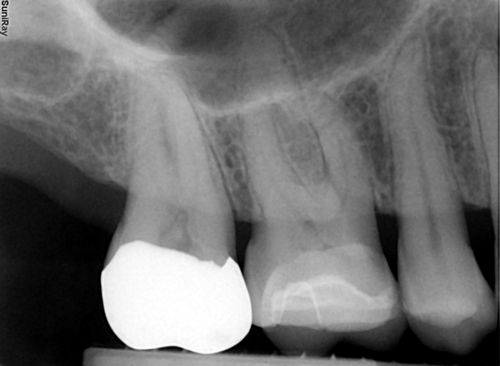

Kodak RVG6100

-20 lp/mm